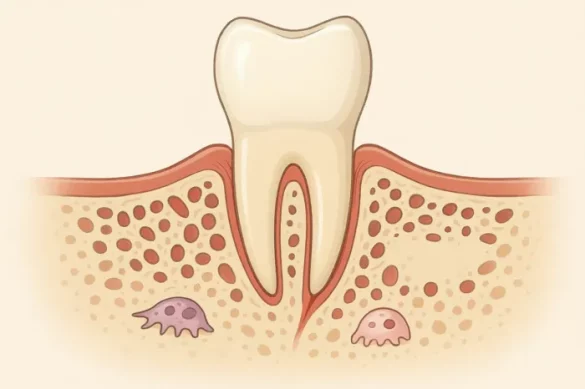

The alveolar bone, occasionally referred to as the alveolar process, is a thick bone shape in each the higher (maxilla) and decrease (mandible) jaws. It carries sockets that keep the roots of the enamel. In easy terms, it’s far the direct anchor for each unmarried teeth for your mouth. Without the alveolar bone, enamel could now no longer have a strong foundation, making critical sports like chewing, biting, and talking almost impossible.

The alveolar bone sits proper above your pinnacle row of enamel and simply underneath your backside row. In the higher jaw, it is determined underneath the maxillary sinus, even as withinside the decrease jaw, it rests above the bottom of the mandible. This bone has major parts—an outer compact layer referred to as cortical bone and an internal spongy, or trabecular, bone. These paintings collectively to create each energy and a few flexibility. This specific mixture lets in the alveolar bone to resist first rate forces whilst we chew.

The number one position of the alveolar bone is to stable the enamel. Specialized collagen fibers, referred to as Sharpey’s fibers, anchor the roots of each teeth into this bone. These fibers are extensions of the periodontal ligament, a tissue that connects the teeth to the encircling bone. Thanks to this anatomy, the enamel are saved firmly in place, prepared to address the stress of day by day sports.

In addition to bodily stability, the alveolar bone additionally acts as a surprise absorber. As we consume or speak, stress is implemented to enamel, which then shifts to the alveolar bone. Its shape lets in for a stability among firmness and the capacity to barely soak up impact, stopping harm to each enamel and jaw.